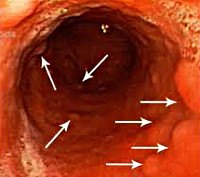

Диагноз устанавливается с учетом жалоб, истории заболевания, внешнего осмотра, пальпации живота, лабораторных и инструментальных исследований. Из-за неспецифичности симптоматики возможно позднее выявление лимфомы желудка, в литературе описаны случаи, когда временной период между появлением болей в эпигастрии и постановкой диагноза составлял около 3 лет. Основным способом инструментальной диагностики является гастроскопия, позволяющая определить расположение и тип роста опухоли. При проведении эндоскопического исследования лимфому желудка может быть трудно дифференцировать с раком, гастритом и немалигнизированной язвой.

Для уточнения диагноза эндоскопист осуществляет забор материала для последующего гистологического и цитологического исследования. Отличительной особенностью взятия эндоскопической биопсии при лимфомах желудка является необходимость забора ткани с нескольких участков (множественная или петлевая биопсия). Для определения распространенности онкологического процесса осуществляют эндоскопическое УЗИ и КТ брюшной полости. Для выявления метастазов назначают МРТ грудной клетки и МРТ брюшной полости. Несмотря на диагностические затруднения, из-за медленного роста большинство лимфом желудка выявляются на первой или второй стадии, что увеличивает вероятность благополучного исхода при данной патологии.